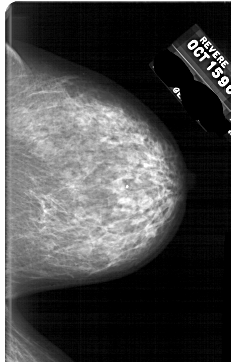

A_1668_1.RIGHT_MLO

RIGHT_MLO LINES 5866 PIXELS_PER_LINE 3736 BITS_PER_PIXEL 12 RESOLUTION 43.5 NON_OVERLAY